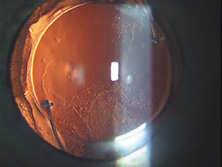

Because of these compounding developments, David Apple began his important work with Randy Olson and in 1983 founded the Center for Intraocular Lens Research at the University of Utah. They were a uniquely qualified combination. Dr. Apple was board certified as both a pathologist and ophthalmologist; Dr. Olson was an academic ophthalmic surgeon. Much like Harold Ridley and Peter Choyce, they began their dedicated quest to improve the condition of pseudophakia. They solicited autopsy specimens and wrote innumerable articles about IOL design, centration, and complex IOL–ocular interactions. One of their most important articles, published in 1985, was a position article citing the advantages of capsular bag placement and recommending it over ciliary sulcus placement, still a controversial issue at the time.44 The eyes submitted to them that year demonstrated capsular bag fixation in 31%, ciliary sulcus fixation in 11%, and asymmetric bag–sulcus fixation in 58%.45 At that time, 85% of surgeons still preferred planned ECCE as their surgical technique.46 While in Utah, Apple and Olson saw the problems created by ARTs solved with the invention of capsulorrhexis, almost simultaneously reported in 1986 by four surgeons from around the world. Two presented articles at the Welch Cataract Congress in Houston that year, and two reported their techniques independently. The discovering surgeons in alphabetical order are Drs. Calvin Fercho (Welsh Cataract Congress, Houston, 1986), Howard Gimbel (video presentation at the annual meeting of the ASCRS in Boston, 1985),47 John Graether (Welch Cataract Congress, Houston, 1986),48 and Thomas Neuhann (video presentation at the meeting of the German Ophthalmological Society in Heidelberg, 1985).47 With this technique, and the creation of an approximate diameter of 5 mm, symmetric placement of any IOL could be guaranteed. It still took several years for the majority of ophthalmologists to incorporate continuous curvilinear capsulorrhexis (CCC) into their surgical routines. In 1988 Dr. Apple relocated the laboratory to the Storm Eye Institute at the Medical University of South Carolina in Charleston. Reflecting new challenges, his laboratory name would be changed to the Center for Research on Ocular Therapeutics and Biodevices. From there, he and his staff, residents, and research fellows continued to receive autopsy specimens from around the world and eventually demonstrated, in the largest autopsy specimen study to date, a decline in asymmetric placement to only 10% of eyes with foldable lenses submitted in 1998.45 Early in his work there, Dr. Apple recruited Dr. Kensaku Miyake's retrociliary photographic analysis method to locate and analyze IOL placement within the eye (Fig. 18). With increasing video sophistication and use of the process by Dr. Apple and his colleagues, Dr. Miyake himself generously expanded the name of the procedure to be called the Miyake-Apple technique. After cancer was diagnosed in Dr. Apple and he was successfully treated, the center was relocated to Salt Lake City in 2002, where it has been permanently designated as the David J. Apple, MD, Laboratories for Ophthalmic Devices Research. In the days when the laboratory was in Charleston, Dr. Apple worked with industry representatives and surgeons to refine IOL design to ensure that capsular bag residence would be as consistent as possible, thereby reducing lens contact with other eye structures in both routine and complicated situations (Figs. 19 and 20). J.A.D. had the great pleasure of working with him in his laboratory to help improve an already sophisticated haptic configuration in a one-piece all-PMMA IOL. At that time, we thought that the entire haptic should be C-shaped so that even its distal end could be recruited for capsular equatorial support (Fig. 21). We studied resistance to haptic compression, attempting to make it softer and more uniform through diameter reductions from 13.0 to 11.5 mm 2.5 mm (Fig. 22). These efforts contributed to the development of the Pharmacia model 811, which, along with others of its day, may have represented the height of single-piece PMMA IOL development (Fig. 23).49